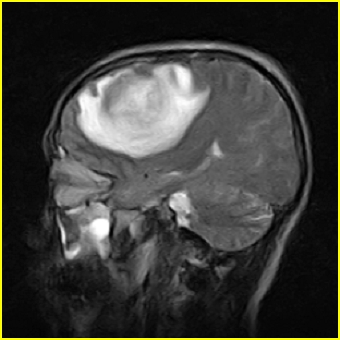

男,45岁,头部剧烈疼痛伴呕吐5天。

右侧额叶见较大的类圆形长t1信号环绕等t1环影,长t2信号环绕短等t2环,周围见明显水肿占位征,中线结构左移,男,45岁,头部剧烈疼痛伴呕吐5天。

右侧额叶,见一占位病灶,t1像病灶、水肿长t1;其间为短t1环行信号。t2像病灶、水肿长t2,其间为短t2环行信号。占位效应明显,中线左移,右测脑室受压闭塞。结合患者发病较急。首先考虑:右侧额叶脑脓肿形成。鉴别:1、转移瘤,多发多见2、胶质瘤。建议增强

t1加权肿瘤呈低信号,肿瘤壁呈等信号.t2 加权时肿瘤呈高信号,肿瘤壁呈等信号.

考虑1脑脓肿.2恶性胶质瘤.